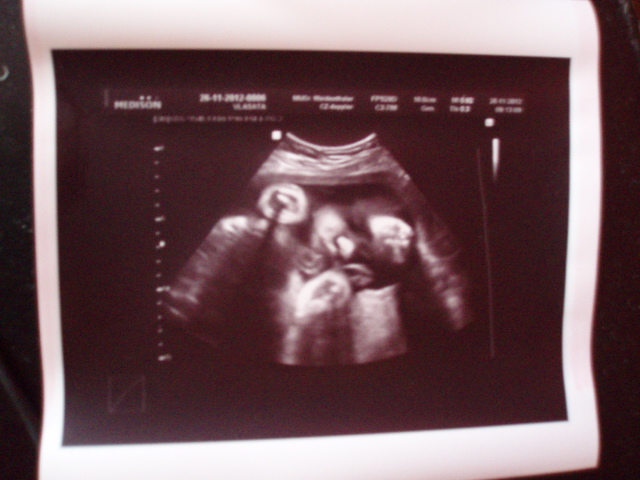

Ted jsme dojeli z gyndy,dělal mi ultr. jsem 32.týden,jsem hrozně ráda,že ta cukrovka vypadá,že na malou nemá žádný vliv,protože váha je akorát ,měla jsem hrozný strach,že bude velká,to by znamenalo problémy ,ale vše je prý ok :-)))) tak mi spadl kámen ze srdce..Má 1892 g. Tatka byl taky na ultr.tak se doktor překonával,ukazoval nám i prutok krve v pupeční šnůře,i jsme to slyšeli,znělo to jak dost drsnej metal

i srdíčko jsme si poslechli,bylo to super .Poprosila jsem ho o fotečku a dost dlouho se teda snažil,to se musí nechat...ale výsledek za těch 50.kč stál ..ten obličejíček tam jde jasně vidět ,prý má jednu pěstičku na čele a druhou pod bradou,že si na ní leží ... Sestřička mmi pak vbutila nějaké vitamíny na pálení žáhy a protože na to fakt dost trpím a stálo to jen 65.kč,tak jsem si je vzala,no snad to pomůže

jé Máre...to je dobrá fotečka....ten obličejíček tam fakt jde vidět nádherně

Mare tééda to je parádní fotka a obličej je tam vážně jasně vidět.. já s tím mám pokaždý problém něco tam najít ale tahle fotka je krásně rozeznatelná..

Máre moc pěkná fotečka

Mare nadherna fotecka ...opravdu se povedla a malinka je kouzelna

Máré to je čupr fotečka

malá na ní vypadá kouzelně